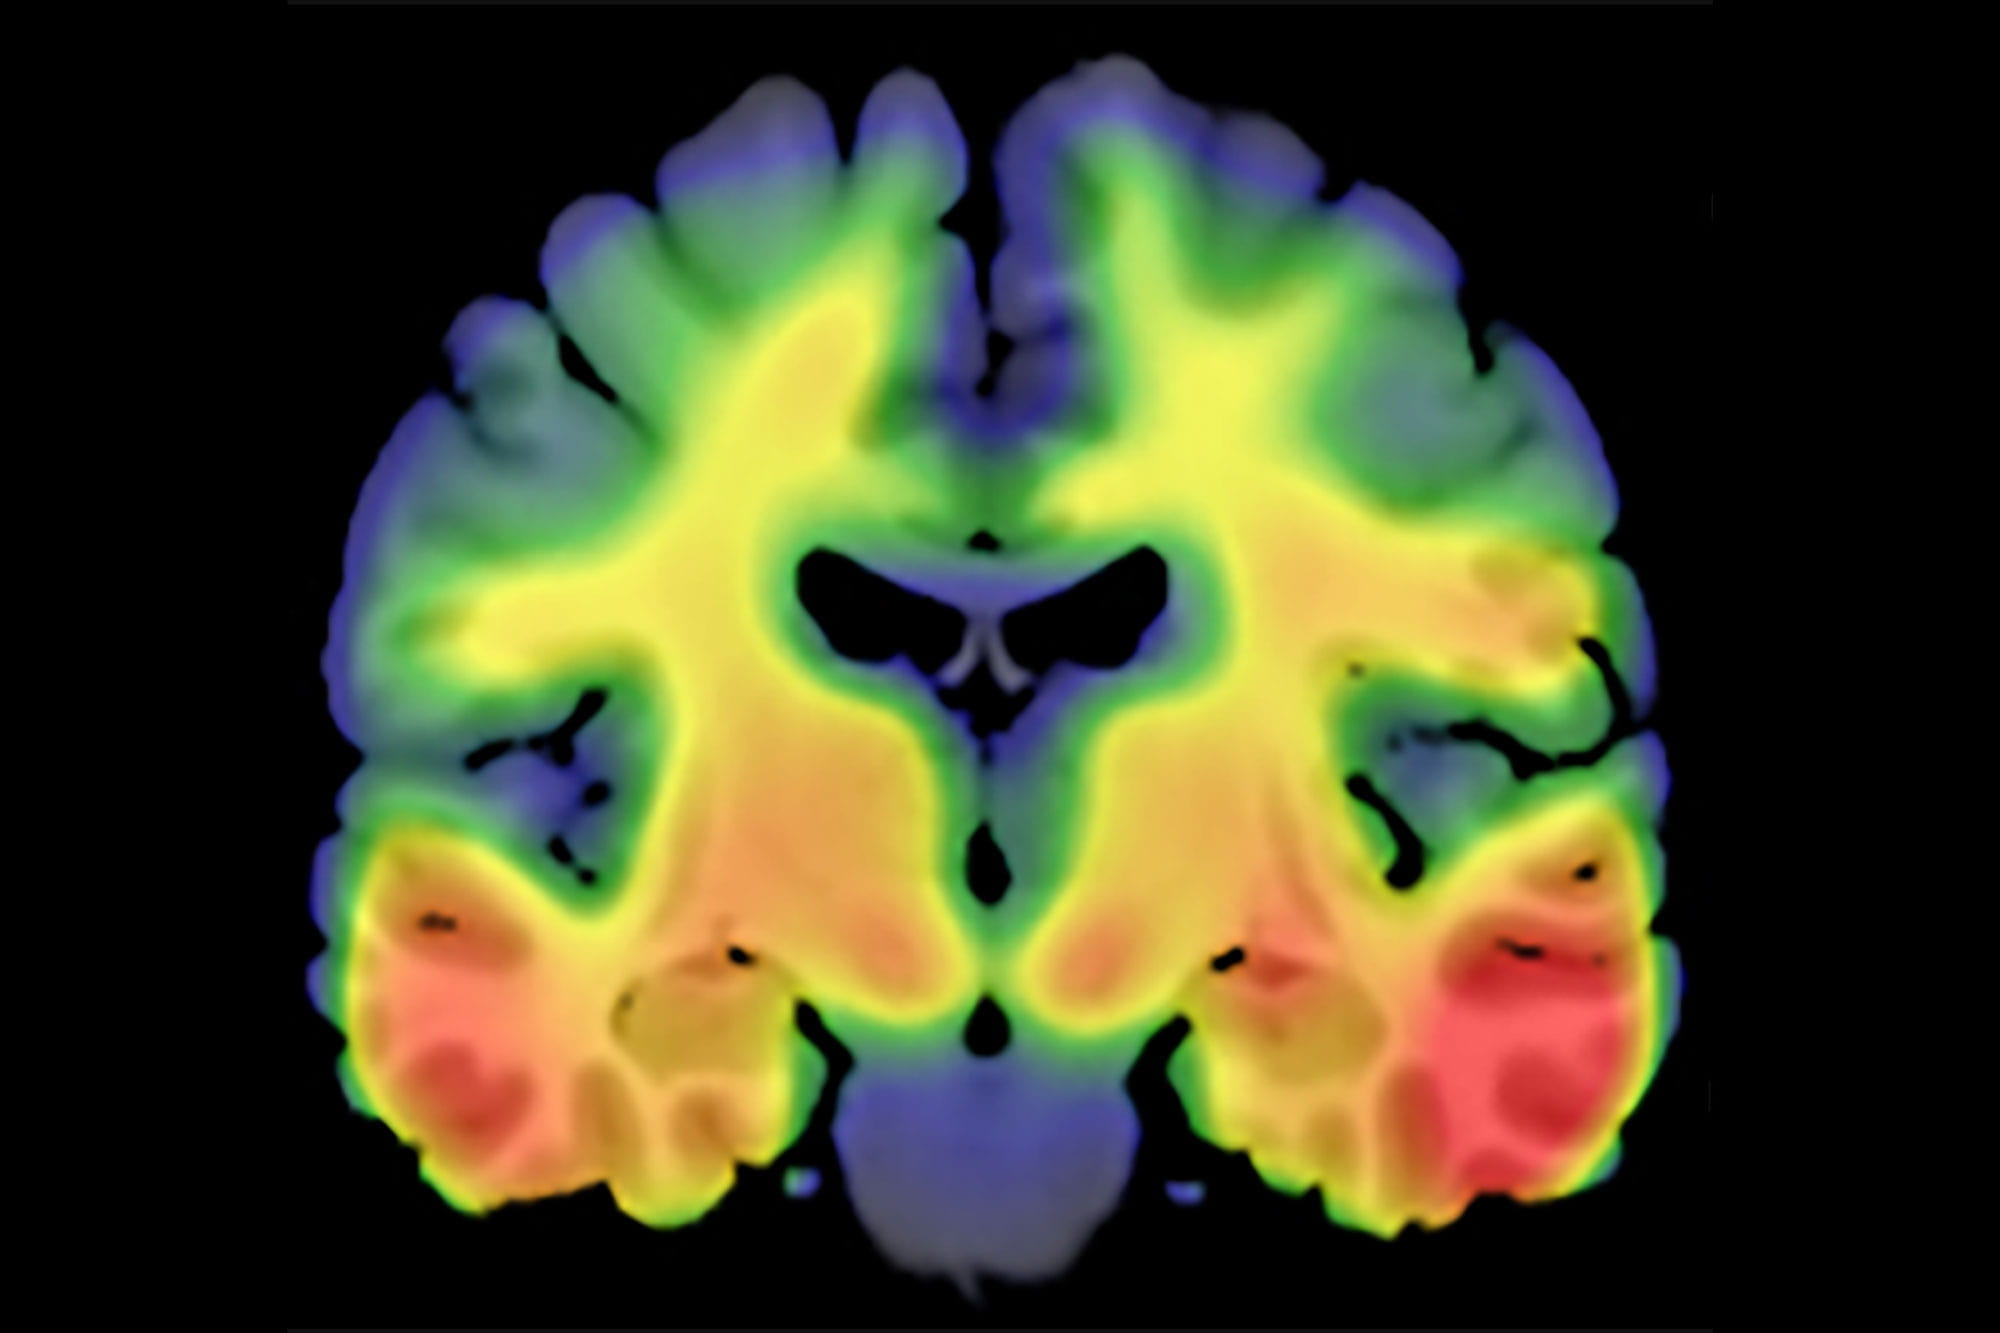

Newly discovered genetic marker could pave the way for future Alzheimer's disease therapeutics

Researchers have identified a new genetic marker that could play a role in the development of Alzheimer's disease and pave the way for novel therapeutic targets and diagnostic tools for the disease.